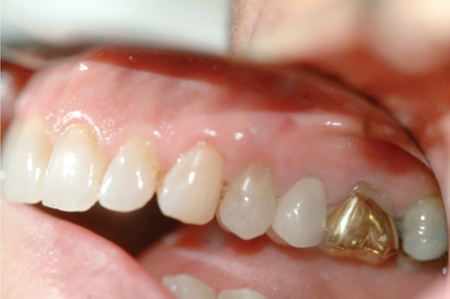

Periodontal And Prosthodontic Management Of Class III Malocclusion: A Case Report

Introduction Modern implant dentistry has been shown to yield excellent well-documented long-term results, with 10-year success and survival rates above 95%.1 Dentists now have the choice of using an array of preoperative planning tools, both conventional and computer-aided, to help them assess potential rehabilitative treatment solutions for their patients. Diagnostic wax-ups have been a critical … Read more